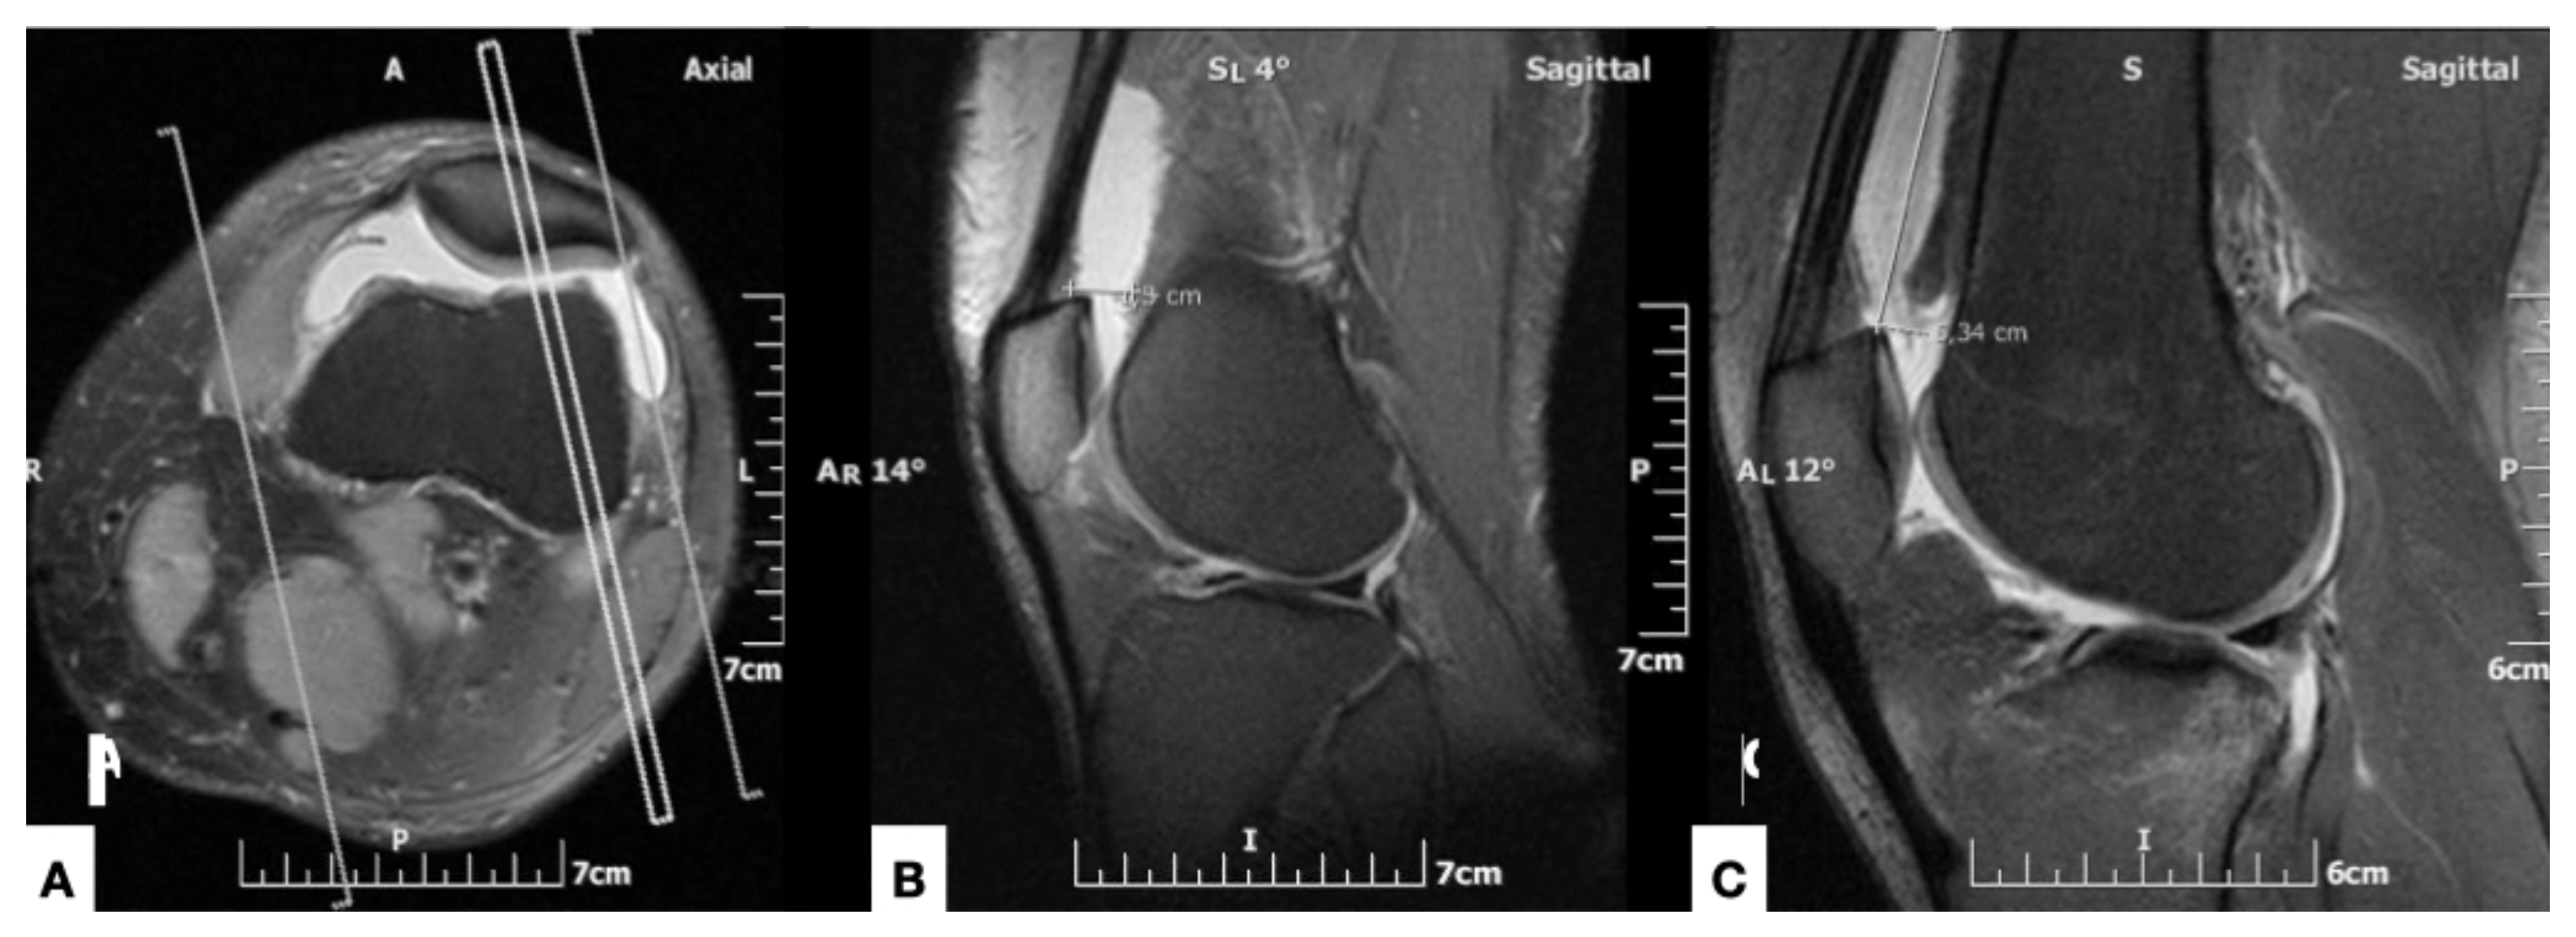

健康・医学 MRI ARTHROSCOPY and SURGICAL ANATOMY Diagnostic。Normal MR Imaging Anatomy of the Knee - Magnetic Resonance。Arthroscopic Core Decompression With Allogeneic Bone。原書 MRI ARTHROSCOPY and SURGICAL ANATOMY OF JOINTS David W Stoller 磁気共鳴画像法、関節鏡検査、および外科的解剖アトラス20数年前Williams & Wilkins本社から直接US$289.00で購入したものです。MRI-Arthroscopy Correlation of Knee Anatomy and Pathologic。 MRI 関節鏡検査機器及び詳細な外科的治療解剖解説図が三次元的に取り入れられて大変解りやすく紹介されている 整形外科を学ぶ上で必須な専門書です。第2版 現代の量子力学 上下巻セット。 下記の説明文参照してください。ACLS 二次救命処置 マニュアル 2020年版。 【このアトラスには、磁気共鳴画像法、関節鏡検査、および外科的解剖で見られる肩、足首、股関節、膝、手首、肘の解剖学的構造が生き生きと描かれています。健康・医学 HUMAN BIOLOGY SEVENTEENTH EDITION。 このアトラスには、500 件を超える MRI スキャンと 200 件を超えるフルカラーの関節鏡検査および外科的解剖写真が掲載されており、MRI、関節鏡検査、外科解剖学の間の直接的な相関関係が示されています。裁断済 日本集中治療医学会 専門医テキスト 第4版。 死体の関節の MRI スキャンは、同じ死体標本の関節鏡および外科的解剖写真と並べて表示されます。「野口晴哉著作全集 第一巻 初期論集一』。 各章は、関節鏡検査と外科解剖学に関する著名な整形外科医による解説から始まります。大腿骨近位部骨折 : 大腿骨頚部・転子部・転子下骨折の手術手技 裁断済。 MRI、関節鏡検査、および関節の外科的解剖学は、付属のCD-ROM でも解説されています。健康管理士一般指導員 テキストセット。CD-ROM - 1999年1月15日by デビッド・W・ストーラー (著者) この見事なマルチメディアCD-ROMには、ストーラー博士の鮮やかなイラスト入りMRI、関節鏡検査、関節の外科解剖学の本の全文とすべてのイラストに加えて、関節鏡のデモンストレーションと死体解剖の約30分のビデオが含まれています。先天性心疾患の外科治療 形態の理解と最良の三次元的再構築。さらに、このCD-ROMには、筋骨格系MRIの多くの重要なトピックに関する第一線の専門家によるナレーション付きチュートリアルが含まれています。初版 医学的心理学 E. クレッチマー 西丸四方・高橋義夫訳 みすず書房。ユーザーは、290枚の4色の解剖線画、関節鏡写真、外科解剖写真を含む800以上の画像にワンクリックでアクセスできます。【裁断済】外鼻形成術・鼻中隔矯正術。ユーザーは、章、キーワード、またはトピックで検索し、すべての画像をズームアップして詳細に表示できます。ジャスミン8 NYSORA神経ブロックマニュアル 裁断済。】